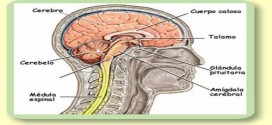

La apalia. Anulación o pérdida de las funciones de la corteza cerebral. Afecciones del sistema nervioso central, cerebral, etc, de probable patogenia autoinmune, genética, traumática, etc, que se caracteriza por placas de desmielinizacion seguidas de esclerosis (endurecimiento o induración morbosa de los tejidos), localizadas en la sustancia blanca del encéfalo y médula, o no en placas ni esclerosis, a saber. …

La analgognosia. Trastorno del lóbulo parietal que incapacita la localización de un dolor y su naturaleza. Afecciones del sistema nervioso central, cerebral, etc, de probable patogenia autoinmune, etc, que se caracteriza por placas de desmielinizacion seguidas de esclerosis (endurecimiento o induración morbosa de los tejidos), localizadas en la sustancia blanca del encéfalo y médula. La analgognosia (asimbolia al dolor). La …

La apraxia. Alteración de la normal actividad con pérdida de la capacidad del uso o manipulación de los objetos habituales, como peinarse, coger una escoba, vestirse, hablar, etc. El origen de la apraxia es una lesión de la corteza cerebral sin que concursen trastornos sensitivos o motores elementales, a saber. Es un trastorno del cerebro y del sistema nervioso en …

La anoia. Demencia, estupor, etc. Afecciones del sistema nervioso central, cerebral, etc, de probable patogenia autoinmune, etc, que se caracteriza por placas de desmielinizacion seguidas de esclerosis (endurecimiento o induración morbosa de los tejidos), localizadas en la sustancia blanca del encéfalo y médula. Trastornos causados por degeneración de las neuronas motoras en todos los niveles del sistema nervioso central, etc, …

La anestia. Trastorno e incapacidad por parte de un sujeto de vestirse; suele estar causado por un trastorno de tipo psíquico. Afecciones del sistema nervioso central, cerebral, etc, de probable patogenia autoinmune, genética, traumática, etc, que se caracteriza por placas de desmielinizacion seguidas de esclerosis (endurecimiento o induración morbosa de los tejidos), localizadas en la sustancia blanca del encéfalo y …

La adiadococinesia. Dificultad o incapacidad para controlar o efectuar ciertos movimientos musculares, especialmente a la hora de detener un impulso y sustituirlo por otro opuesto. Puede observarse en trastornos neurológicos del cerebelo. La adiadococinesia es, la incapacidad para realizar con rapidez movimientos alternantes sucesivos por ejemplo, la pronación y la supinación de la mano. Es una exploración fácil y una …